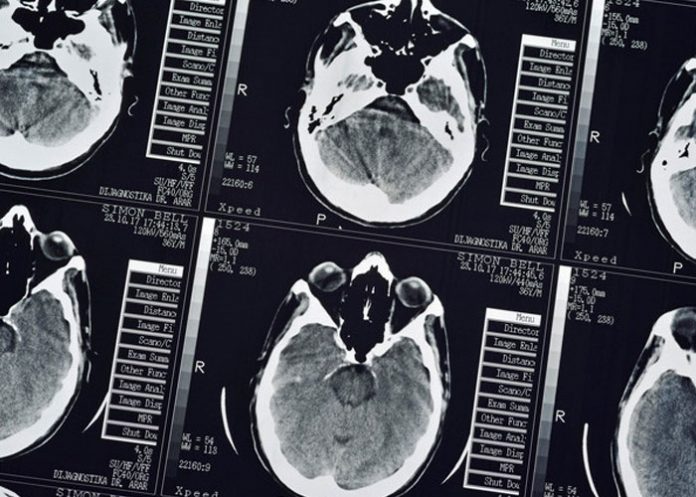

Médicos de la província de Zhejiang (China) encontraron que un hombre de 43 años, que se dirigió al hospital tras sufrir dolores de cabeza y convulsiones durante un mes, alojaba en su cuerpo más de 700 tenias, según informó este martes la plataforma Pear Video.

Tras realizar los exámenes médicos, el doctor Wang Jian-rong, del Primer Hospital Afiliado de la Facultad de Medicina de la Universidad de Zhejiang, diagnosticó que Zhu Zhong-fa sufría de teniasis, una enfermedad causada por ese gusano parasitario.

El médico encontró que más de 700 tenias, que el paciente albergó en su cerebro, pecho y pulmones, ya habían causado daños a sus órganos. "Hay múltiples presencias de lesiones que ocupan espacio en el cerebro del paciente. También están en los pulmones y llenan los músculos dentro de la cavidad torácica", señaló Wang.